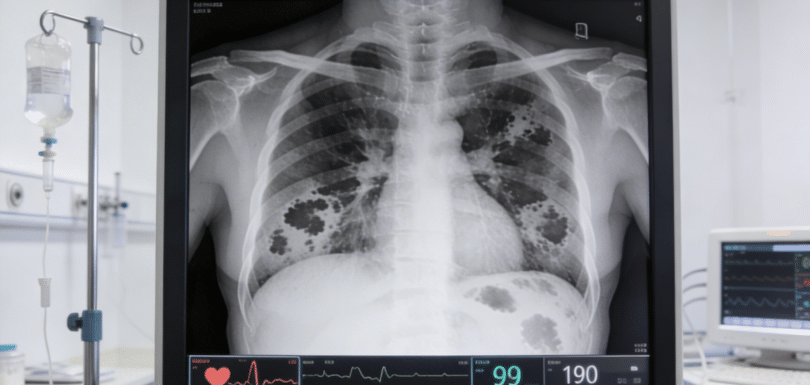

Head CT for Stroke, Hemorrhage, or Trauma Emergency Treatment in Odessa TX | Priority ER – 24/7 Head CT for stroke, hemorrhage, or trauma is a critical diagnostic test required immediately when experiencing sudden weakness, severe headache, altered consciousness, head injury, or neurological symptoms. Priority ER provides 24/7 emergency head CT imaging with zero wait […]